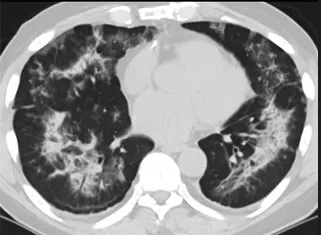

更值得注意的是,有之前应对过武汉新冠疫情的中国权威肺病专家,在查阅了60篇涉及美国“电子烟肺病”病例的研究论文,并对其中142位电子烟肺病患者的250张肺部影像图片、临床信息以及文献原文进行了仔细全面的研究后,发现这些病例中有16个更有可能是新冠肺炎的“疑诊患者”,有5个临床症状和治疗情况相对完整的患者,还被这些专家认定为了“中度可疑”。另外,这16个病例中有12个病例的发病时间,都在2020年以前。

新冠病毒是否来自美国?迄今为止最全面的线索来了

(这4张图,是专家怀疑被误诊为电子烟肺病的其中一个病例的肺片。专家表示,他们不是仅仅通过一张影片做判断的,而是通过这4张涵盖了这名病例肺部多天变化情况的影片进行的研判,认为该病例的病程进展跟新冠更为相似)